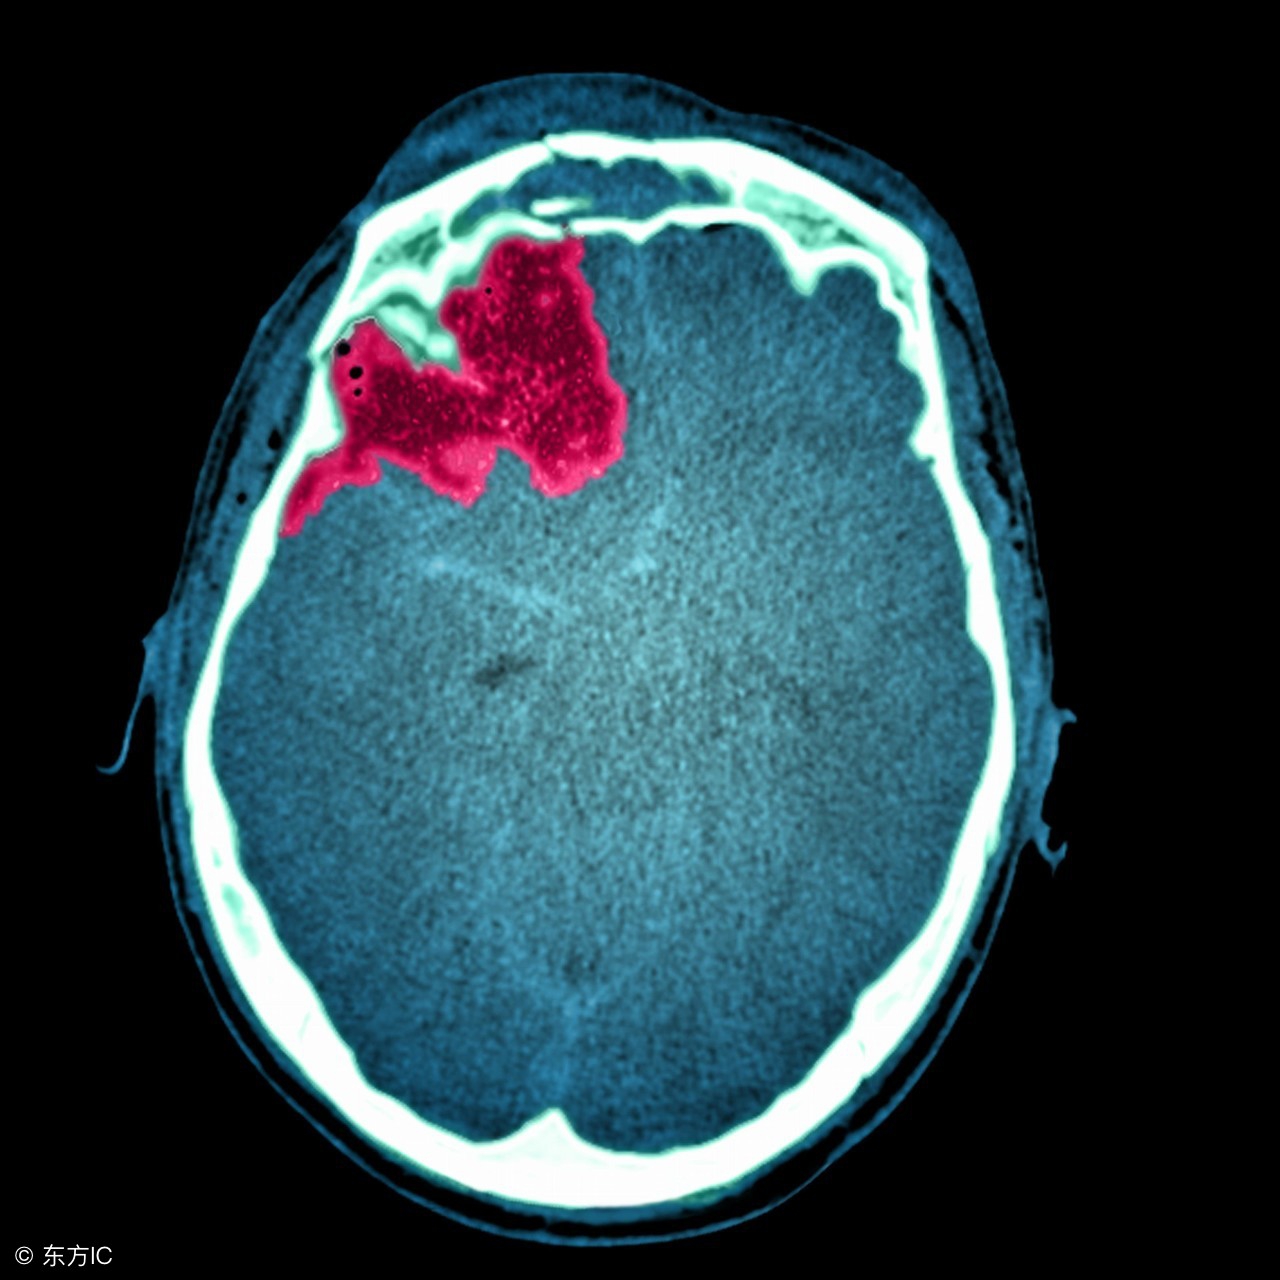

高血压脑出血手术后的饮食

注:文中图片来自网络,如有侵权请联系删除